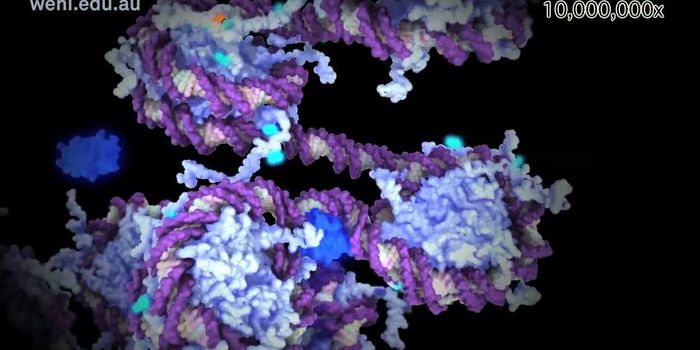

MAY 25, 2022Cell & Molecular BiologyThe words “molecular biology” might sound intimidating to most, but it’s not quite as bad as you think ...